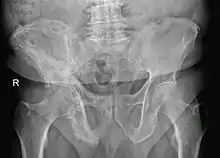

- Pagetic bone has a characteristic appearance on X-rays. A skeletal survey is therefore indicated.

- Bone scans are useful in determining the extent and activity of the condition. If a bone scan suggests Paget's disease, the affected bone(s) should be X-rayed to confirm the diagnosis.

The disease is progressive and slowly worsens with time, although people may remain minimally symptomatic. Treatment is aimed at controlling symptoms, but there is no cure. Any bone or bones can be affected, but Paget's disease occurs most frequently in the spine, skull, pelvis, femur, and lower legs. Osteogenic sarcoma, a form of bone cancer, is a rare complication of Paget's disease occurring in less than one percent of those affected. The development of osteosarcoma may be suggested by the sudden onset or worsening pain.